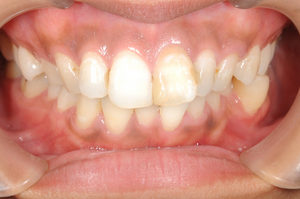

左上3番目の歯がなかなか生えてこないということを主訴に来院された子供さん(13歳)です。 レントゲン写真にて歯の位置を確認しました所、2番目の歯の下に位置しており、かなり方向がずれていることが判明しました。 そこで埋伏歯 […]